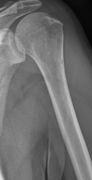

Humerus with multiple myeloma lesions.